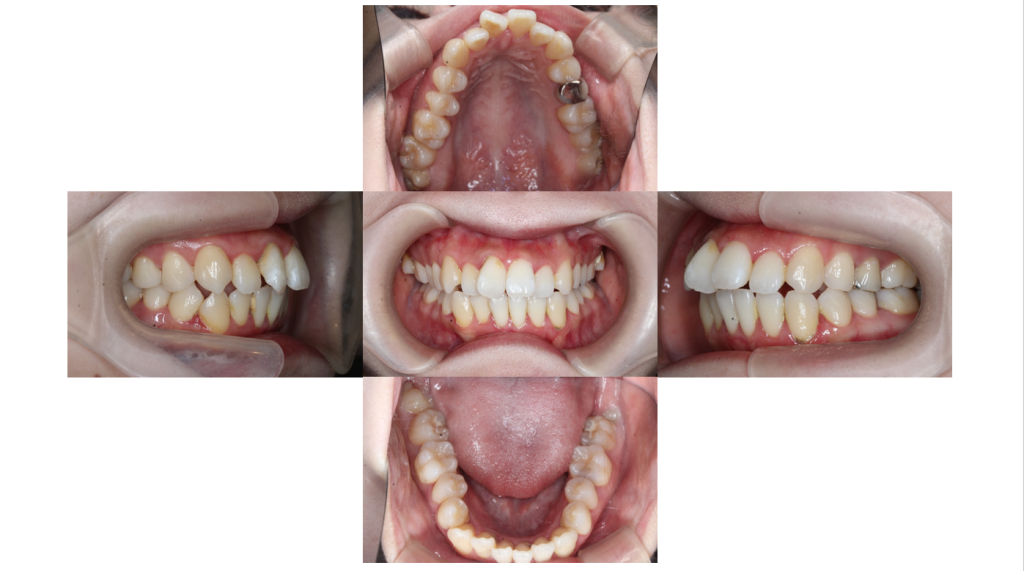

初診

叢生・裏側全体矯正の症例初診時(治療開始前)の口腔内です。